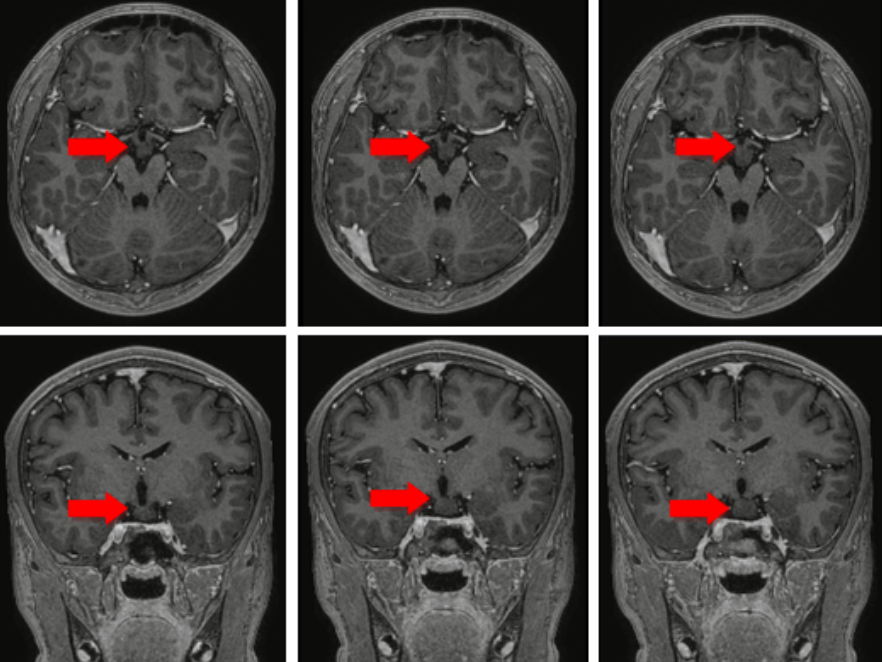

术前头部核磁共振,箭头所示为病变位置

下丘脑错构瘤对于瘤蒂的处理非常关键,处理好瘤蒂才能保证术后的效果。患者三维的头部核磁共振发现病变形态特殊,仅有两个很细的瘤蒂从两侧与脑组织相连,瘤蒂直径最细的地方约1mm,最粗的地方也不超过2mm;如何将直径为0.8mm的电极精准的穿过瘤蒂,成为手术的主要难点,如果有任何哪怕0.5mm的偏差就有可能使电极位置偏移而监测不到异常的放电也无法通过毁损起到彻底阻断放电传导的效果。手术计划最终设计了两根电极,分别沿两侧的瘤蒂长轴穿过,保证对瘤蒂的彻底处理。在成功“消灭”了患者颅内的错构瘤后,将电极安全取出,既保障癫痫灶毁损、又保护了手术的安全性,解决了小文多年癫痫发作的问题。